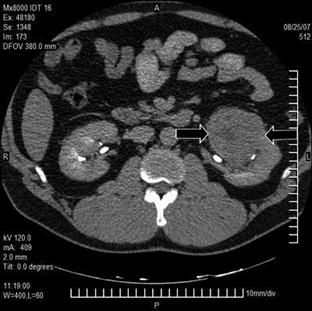

Медицинские изображения и объяснения агенезии почки

Раздел: Снимки-откровения